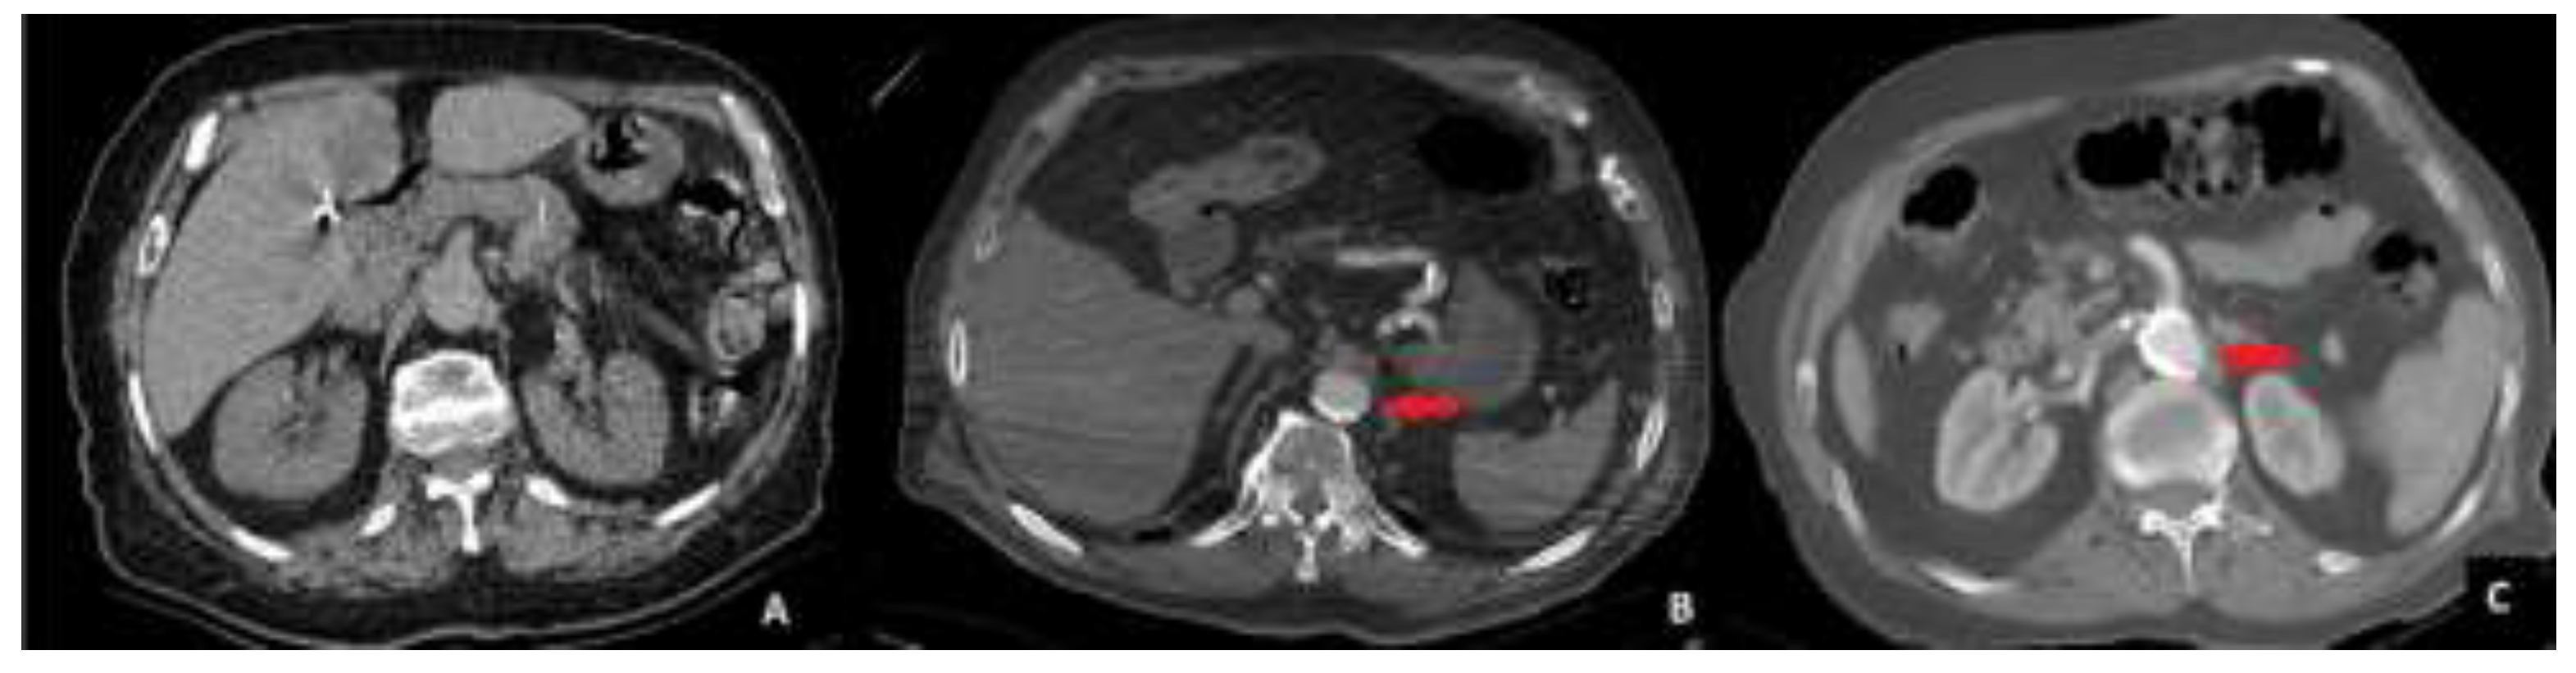

The abdominal CT scans were evaluated for aortic calcification (AC) in the sections between the celiac trunk and the aortic bifurcation. Aortic calcification was classified into three stages based on the extent of calcified plaques encircling the aortic lumen. Stage 0 was defined as the absence of any detectable calcification. Stage 1 was assigned when calcification occupied less than 50% of the aortic circumference. Stage 2 was defined as calcification occupying more than 50% of the aortic circumference.

To ensure consistency in classification, all imaging evaluations were performed by two independent radiologists who were blinded to the surgical outcomes. Any discrepancies in the assessment were resolved by consensus discussion. A visual example of each calcification stage is provided in Figure 1.

Figure 1. Computed tomography images of patients. A-No calcification (Stage 0) B-Calcified area less than 50% of the aortic circumference. (Stage 1) C-Calcified area more than 50% of the aortic circumference (Stage 2). The area of calcification was indicated by a red arrow.